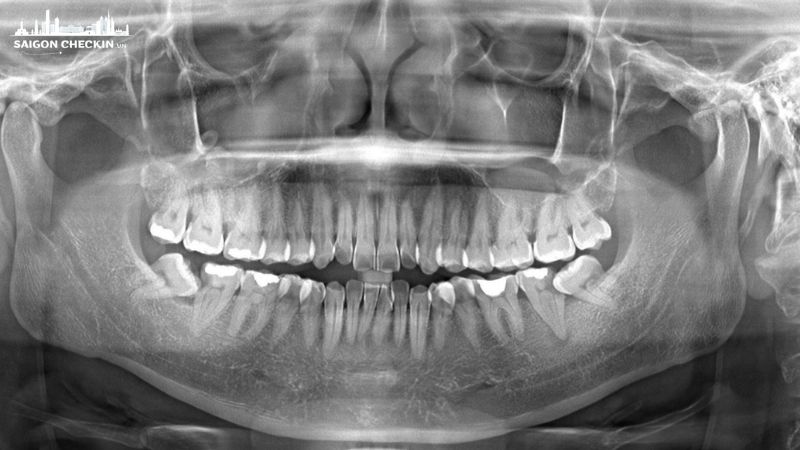

2.1. X-quang răng toàn cảnh Panorama – quan sát toàn bộ răng, xương hàm

Phim Panorama cho phép chụp toàn bộ hai hàm răng, xương hàm trên – dưới và cả cấu trúc khớp thái dương hàm trong một lần duy nhất. Thời gian thực hiện nhanh, chỉ khoảng 5 phút, chi phí dao động 150.000 – 250.000đ/lần. Đây là lựa chọn phổ biến khi bệnh nhân cần khám răng tổng quát hoặc chuẩn bị điều trị chuyên sâu.